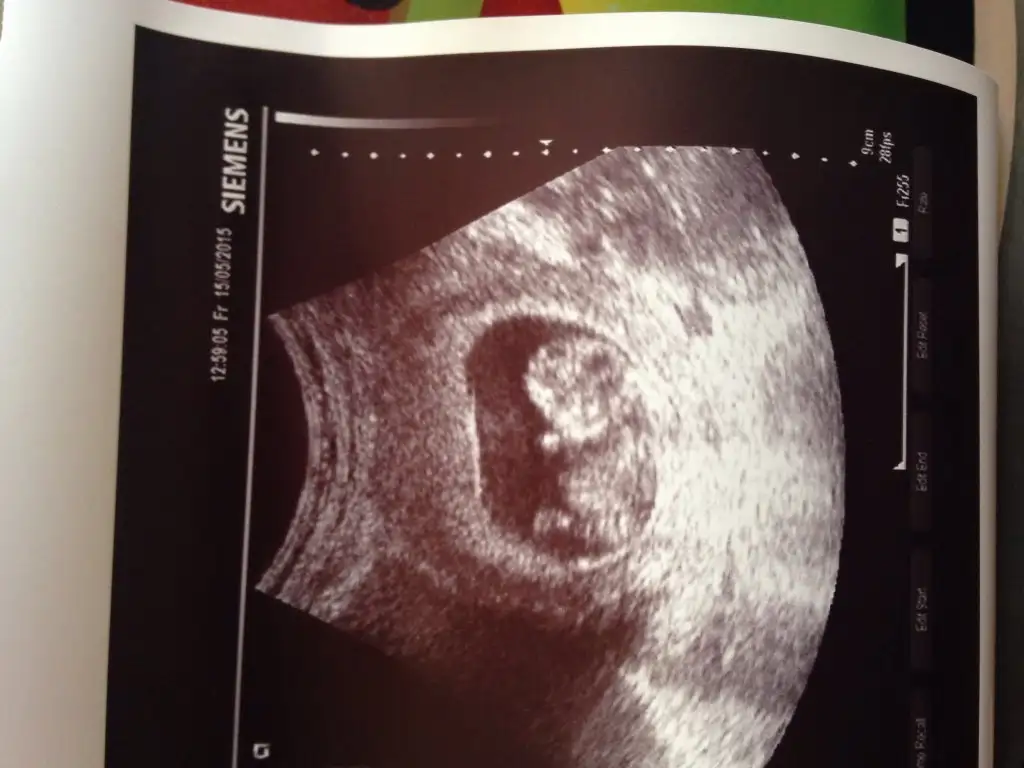

sağol canım ağzına sağlıkCanım seninkini erkek bebeğe benzettim ikinci Fotoğrafın alt kısmında bir şeyler var gibi. Ama bebek arkasını dönmüş bu teori için yandan ya da önden olması lazım Fotoğrafın.

ben nub göremedim. yani anlamadım fotodan

Kiz canimama bende yorum istiyorummmmmlütfen